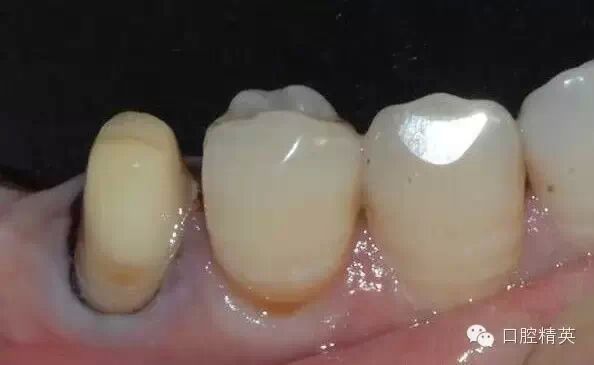

46缺失,不考慮種植牙,45、47做基牙,固定烤瓷橋修復(fù);這是口內(nèi)的情況